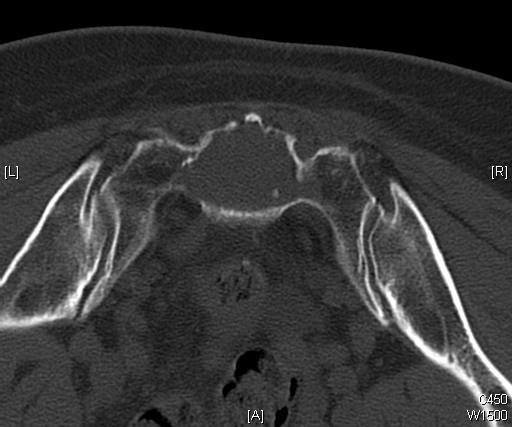

CT (Fig. 11 & 12)

• Destructive bone lesion

• Cortical destruction

• Soft tissue mass is easily detected on a CT scan

• 20% of patients with chordomas shows calcifications

• Subtle calcification are easily detected with CT scan

Fig. 11 & 12: CT scan of a sacral chordoma demonstrates a lytic lesion of the sacrum with a soft tissue mass. Subtle calcifications in the axial CT scan.